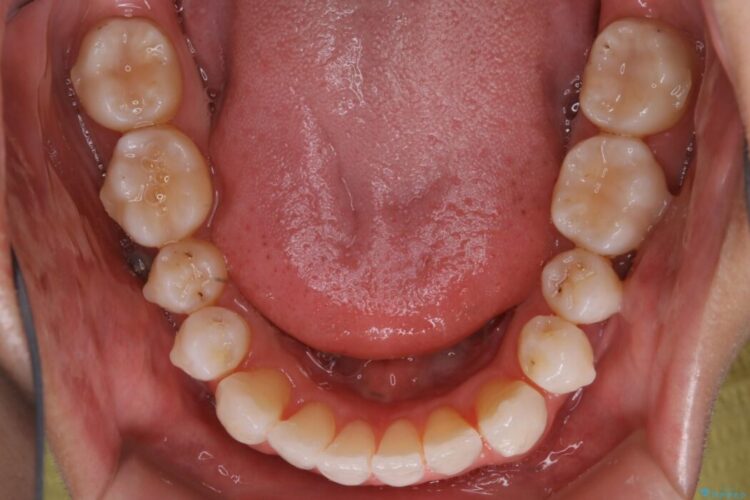

上顎歯列弓のガタガタを治療したいとのことで来院されました。

前に出ていた前歯や目立つ八重歯(3番目の歯)もきれいに並び、奥歯の虫歯治療も並行して行ったため、機能面でも見た目的にも良くなり満足していただきました。